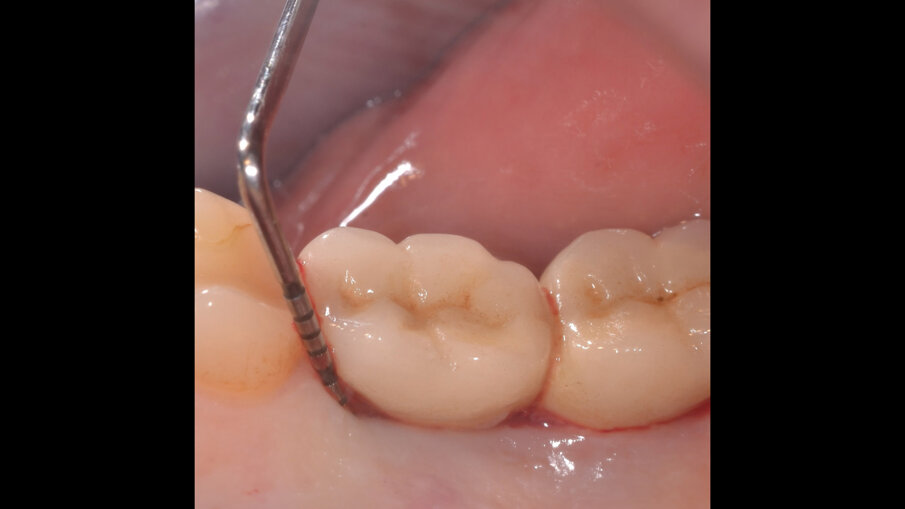

Il paziente, di sesso maschile e di 48 anni di età, è in buone condizioni di salute generale ma, a distanza di 10 anni dall’inserimento, presenta due impianti endossei, in posizione 4.6 e 4.7 con uniforme perdita ossea e con sondaggi di profondità variabile tra 6 e 9 mm accompagnati da sanguinamento, con tessuti marginali che mostrano importanti aspetti infiammatori, causa di sintomatologia dolorosa per il paziente (Figg. 1a-f).

I siti interessati sono stati strumentati per via non chirurgica, utilizzando strumenti manuali, strumenti ultrasonici e air polishing con eritritolo. Al termine della seduta è stato applicato il gel di ozono (Ozosan Gel - Bioactiva) all’interno delle tasche, lasciando agire il dispositivo per 8 minuti, quindi eseguendo lavaggio con soluzione fisiologica. Il post-operatorio ha avuto un decorso privo di dolore con rapida remissione della sintomatologia soggettiva. Il paziente è stato inserito in un programma di mantenimento parodontale trimestrale. A distanza di 6 mesi dal trattamento non chirurgico della perimplantite, i siti si presentano stabili con profondità di sondaggio ridotta tra i 3 e i 5 mm con assenza completa di sanguinamento al sondaggio (Figg. 1g-m).